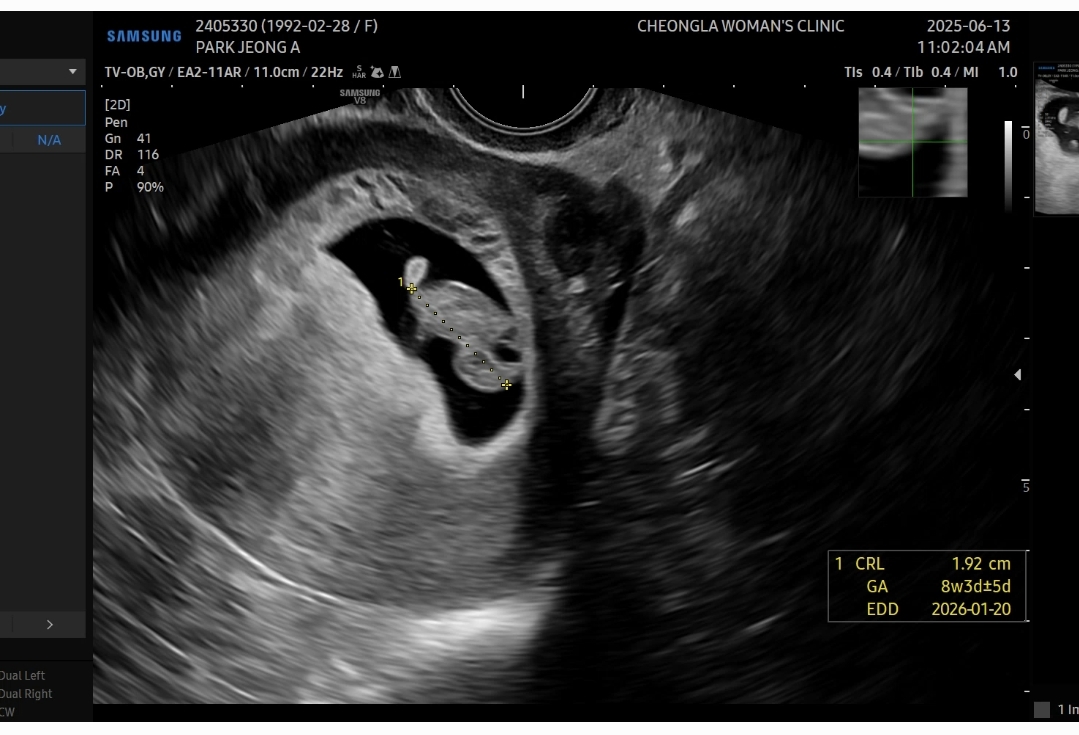

2026년 1월 베동

6주차부터 피비침있어서 계속 약먹고 주사맞다가 어제 핏덩어리 나와서 엉엉울며 병원다녀왔어요ㅠㅠ 다행이 애기는 잘크고있다고 심장소리듣구해서 안심하고있는데 입원하라는거 답답할꺼같아서 일단 집와서 눕눕중인데 눕눕을..처음해봐서 어떻게 해야하는지 어렵네요. 누워있는게 이렇게 힘든건지 처음 알았어요. 밥먹고 소화안되서 앉아있다가 슬금슬금 누웠다가 불편하고 답답해서 다시 앉았다가ㅠㅠ 이렇게 하는게 맞나싶기도하고 입덧도없어서 딱히 힘들지않으니 계속 저도모르게 무리를 했던거같은데 무증상에 걍 누워있으려니 이것도 참 고역이네요ㅠㅠ 모두...12주까지 화이팅해요💚